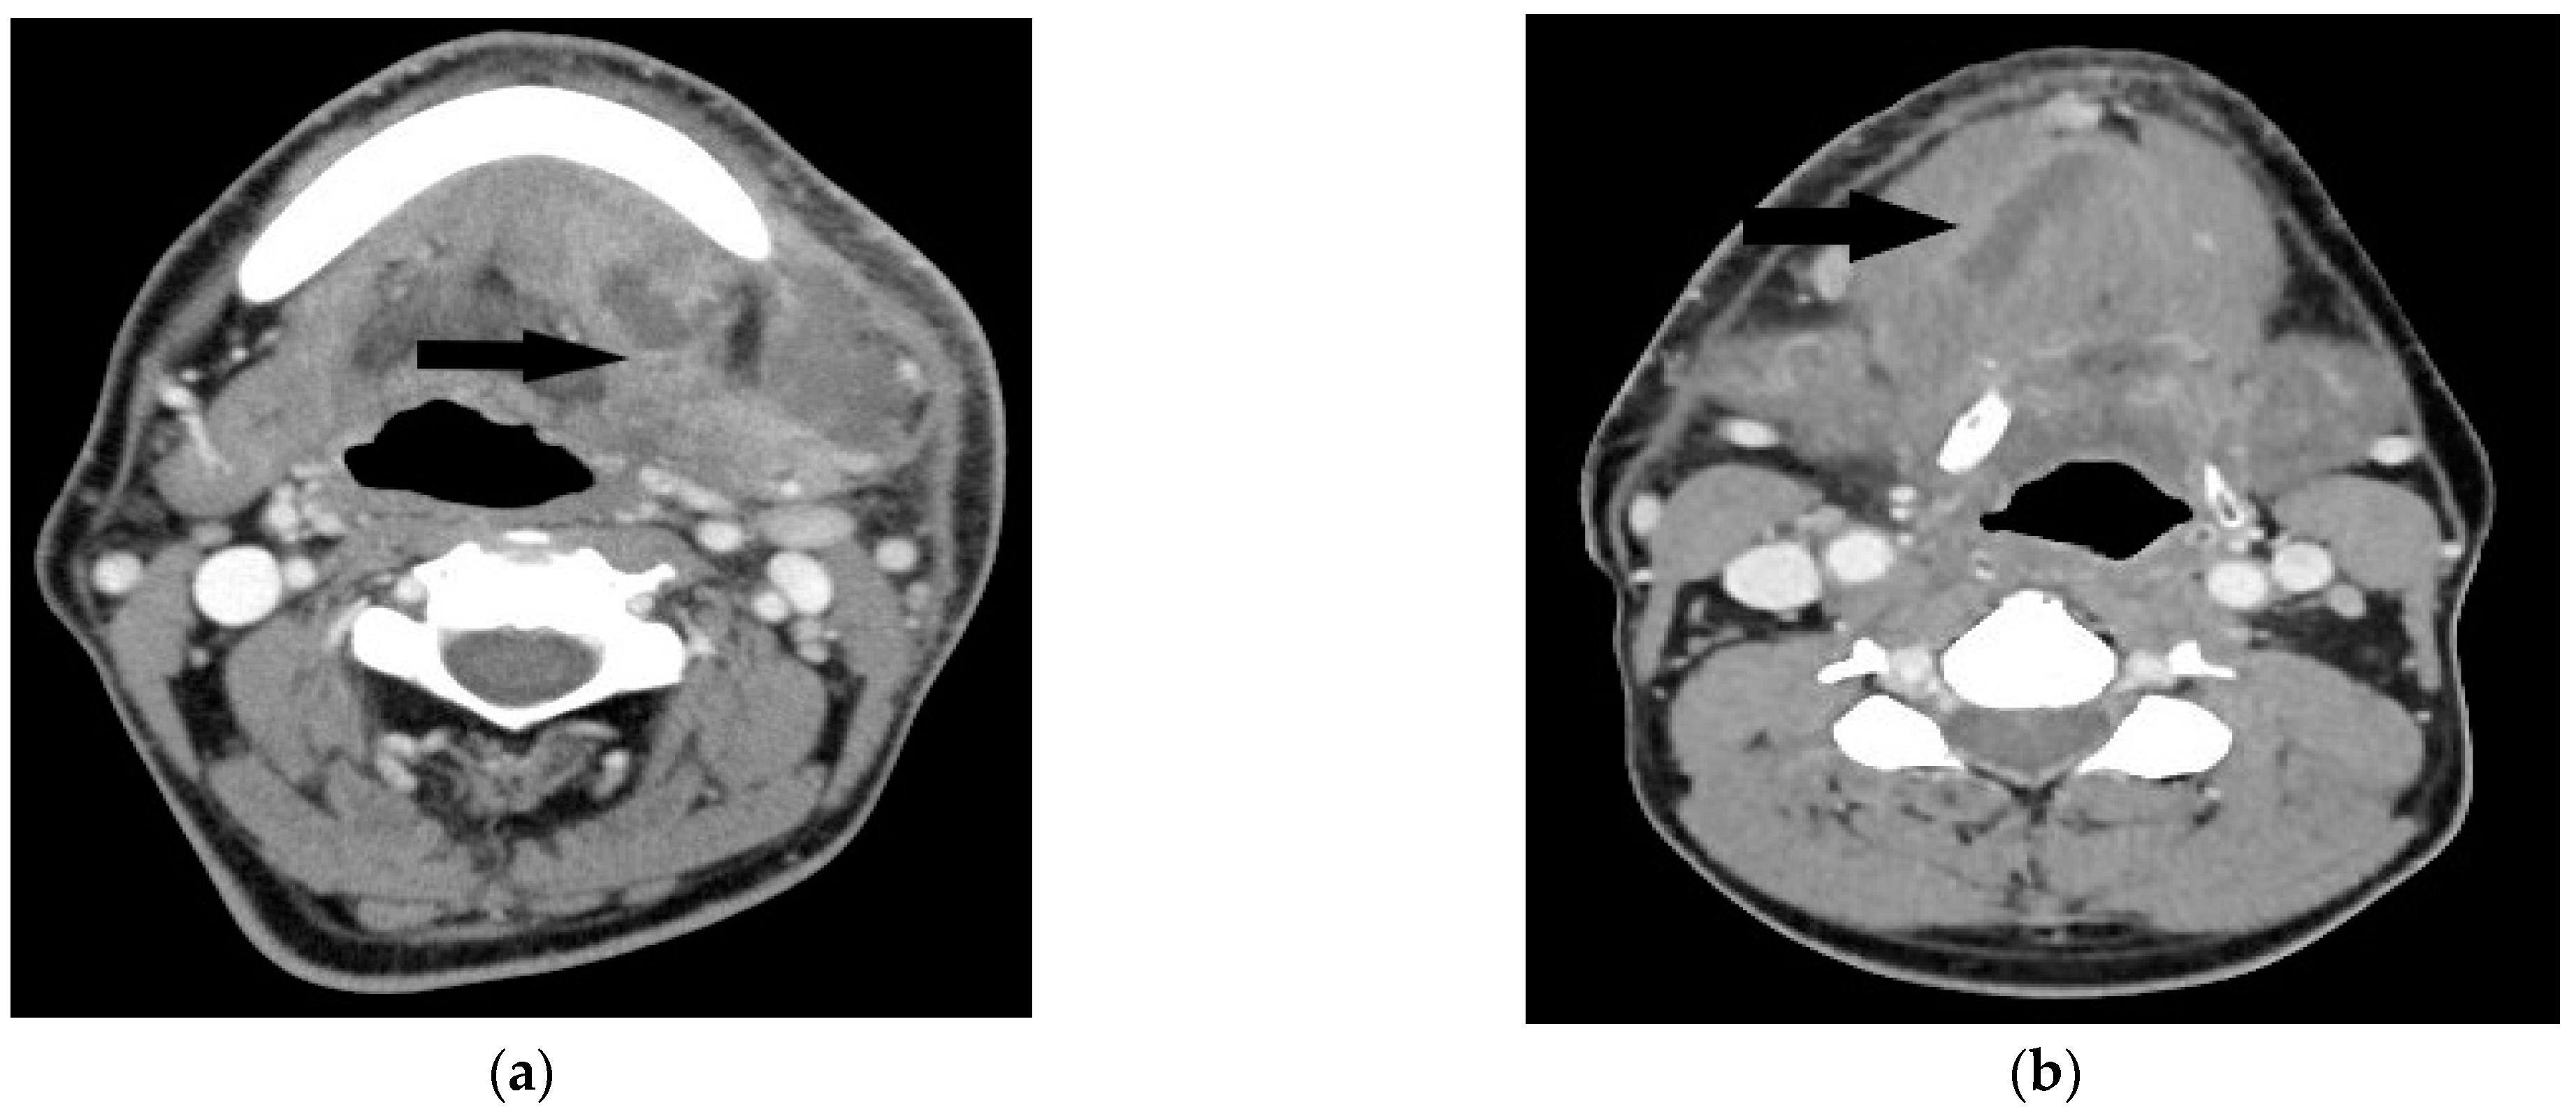

The study was approved by the institutional review board of Chang Gung Memorial Hospital (approval no.202201372B0). We retrospectively reviewed the medical records of patients undergoing surgical treatment of deep neck abscesses from August 2017 to July 2022. Computed tomography (CT) was performed in all patients. Submandibular abscesses are those that extend from the mouth floor to the mandible bilaterally (Figure 1a). Submental abscesses affect the central neck from the floor of the oral cavity to the hyoid bone (Figure 1b). Masticator abscesses extend cranio-caudally between the skull base and mandibular ramus, and transversely between the medial pterygoid and masseter muscles. Parotid abscesses are defined by the presence of pus in and around the parotid gland. The parapharyngeal space contains predominantly fat and is a cone-shaped space from the skull base to the hyoid bone. The peritonsillar space is above the parapharyngeal space and around the bilateral tonsil. Retropharyngeal abscesses are located between the pharynx and vertebra, extending from the skull base to the level of the T2 thoracic vertebra. The anterior visceral space, also called the pretracheal space, lies between the infrahyoid strap muscles and esophagus. DNM can be confirmed on chest CT (Figure 2) and culture from mediastinal fluid drained during surgical intervention. All patients with a deep neck abscess were treated with empiric intravenous antibiotics (Ceftriaxone 1 g Q12H and Clindamycin 500 mg Q8H). Antibiotic treatment was then adjusted based on bacterial culture and sensitivity test. After surgical drainage of the deep neck abscess, the neck wound was irrigated with povidone iodine solution 2–3 times per day according to the wound condition. Thoracotomy was performed in patients with DNM of the anterior inferior and posterior mediastinum. Tracheostomy is not routinely performed in these patients. Tracheostomy is performed in patients with respiratory distress and dependent on endotracheal tube for more than two weeks. Exclusion criteria included patients with neck cellulitis without abscess formation, patients with necrotizing lymphadenitis due to lymph node metastasis, and those without CT images to evaluate the extent of the abscess. Before surgery, lab data including hemoglobulin (Hb), white blood cell count, neutrophil percentage, C-reactive protein (CRP) level, and blood glucose were recorded. Patients’ characteristics including gender, age, etiology, and presenting symptoms were collected. Hospitalization duration and bacterial cultures from the wound were also analyzed. Fisher’s exact test was used to compare nonparametric variables including sex, symptoms at presentation and location of the abscess. Mann-Whitney U test was used to analyze parametric data (age, Hb, WBC, CRP, etc.). The data were analyzed using SPSS for Windows, version 20.0. Statistical significance was defined as p < 0.05.

Figure 1.

(a) Axial contrast-enhanced CT image reveals abscess (black arrow) in the left submandibular space. (b) Axial contrast-enhanced CT image shows a hypodense lesion (black arrow) in the submental space.